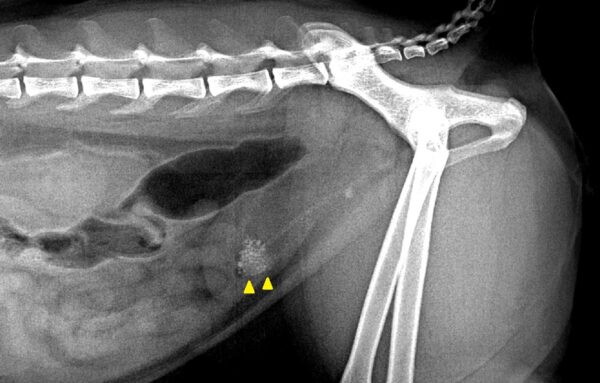

◆ 簡単なケース

・大きくて明瞭な結石が1~2個と少数である

・レントゲンにもはっきり映る